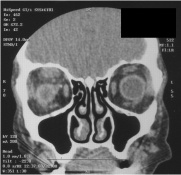

Figure 3a: Amyloidosis causing ptosis Figure 3b: CT scan showing amyloid infiltration of the levator and superior rectus of the right eye

Systemic involvement should be ruled out in any patient who presents with an isolated conjunctival lesion. Amyloidosis can frequently affect the kidney, heart, and liver. Tests for cardiac, liver and kidney function including an echocardiogram and electrocardiogram as well as serum and urine protein electrophoresis should be obtained. More specific immunofixation and free light chain electrophoresis of both the serum and urine should be obtained as well. Other tests such as bone marrow biopsy, abdominal fat biopsy, and rectal biopsy should be considered. Imaging tests such as CT or MRI may be helpful in localizing and detecting the extent of orbital disease.